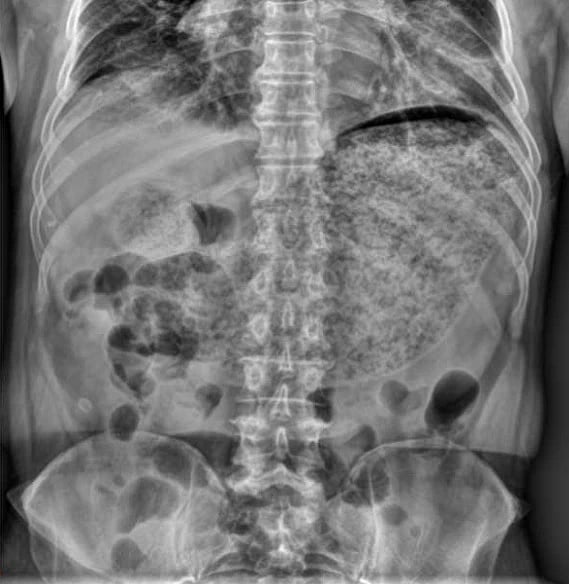

Gastroparesis occurs when the stomach cannot move food into the small intestine at a normal pace. In diabetes, repeated fluctuations in blood glucose can damage the vagus nerve, which controls stomach muscle contractions. Dong Seok Lee1 and Sang Jin Lee/Wikimedia Commons

Gastroparesis occurs when the stomach cannot move food into the small intestine at a normal pace. In diabetes, repeated fluctuations in blood glucose can damage the vagus nerve, which controls stomach muscle contractions. Damage to this nerve slows gastric emptying and leads to symptoms such as nausea, vomiting, bloating, and early satiety.[2]